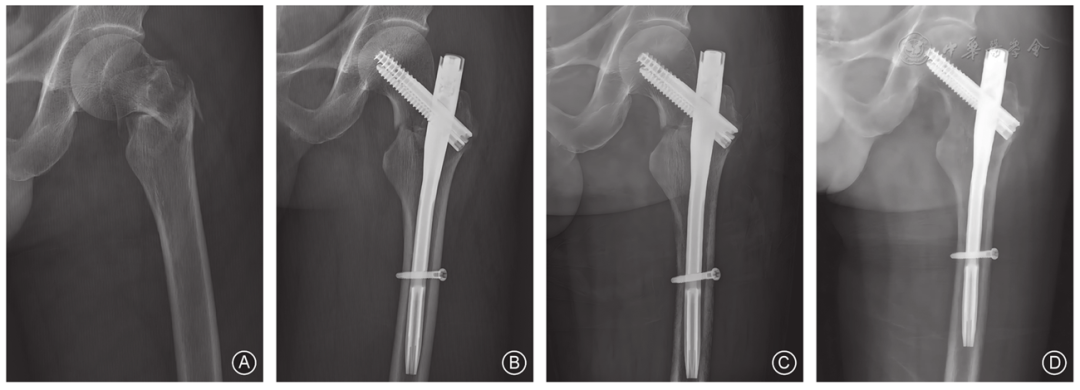

图3 男,72岁,左侧股骨转子间骨折,接受InterTAN内固定治疗 A 术前髋关节正位X线片示股骨转子间骨折 B 术后1周髋关节正位X线片示内固定位置良好 C 术后3个月髋关节正位X线片示初步愈合 D 术后8个月髋关节正位X线片示骨折完全愈合